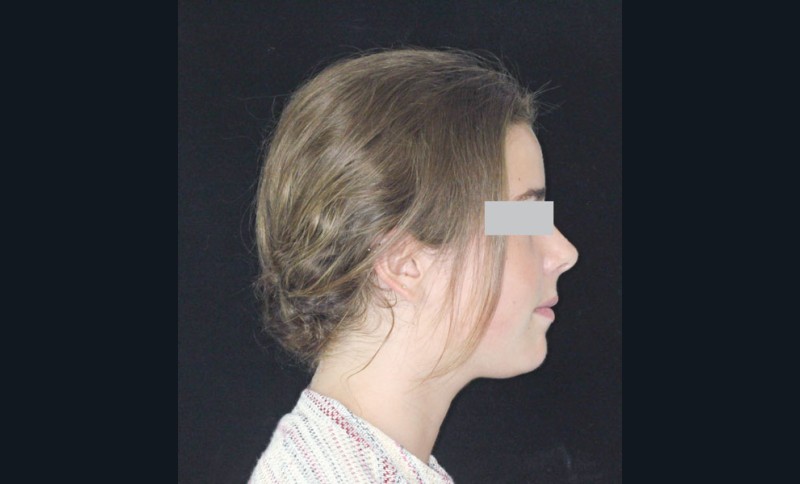

• Obtenir des rapports squelettiques de classe I par réponse de croissance mandibulaire.

• Résoudre l’encombrement intra-arcade par extractions dentaires.

• Obtenir un guide antérieur fonctionnel par idéalisation des rapports incisifs.